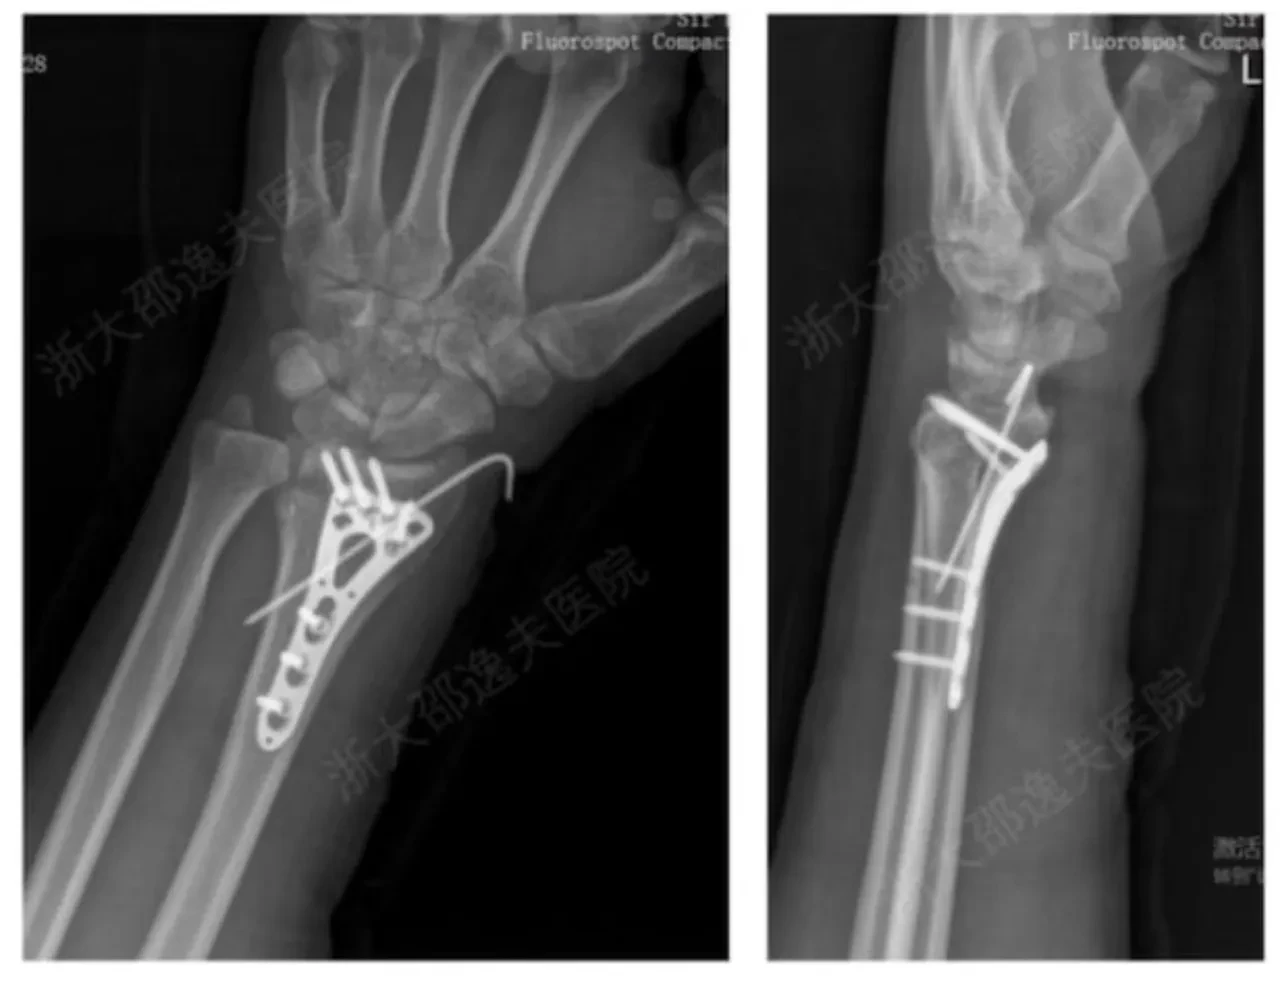

Yöntemin klinik kullanımına ilişkin ilk örneklerden biri bilekteki bir kırık üzerinde gerçekleştirildi. Cho Sun Daily'nin aktardığına göre hastaya yalnızca 3 santimetrelik bir kesi açılarak tek enjeksiyon yapıldı. Sadece üç dakika içinde kemik iyileşti.

Geleneksel cerrahide tercih edilen yöntem, metal plaka ve vidalarla onarım gerektiriyor. Ayrıca bir yıl sonra implantların çıkarılması için ikinci bir ameliyat şart koşuluyordu. Takip sürecinde elde edilen veriler de dikkat çekici. Üç aylık kontrol muayenesinde kırığın tamamen komplikasyonsuz iyileştiği bildirildi.